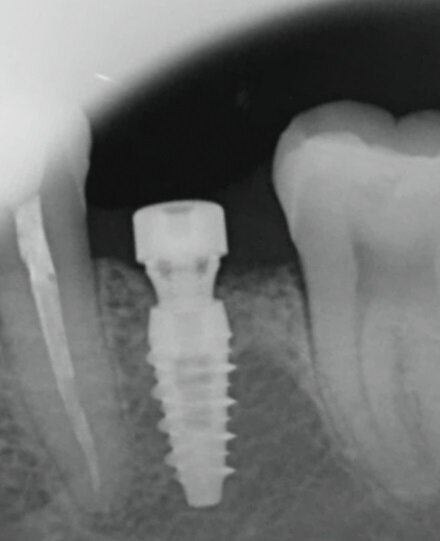

Nello studio sono stati inclusi 20 pazienti (12 donne e 8 uomini) di età compresa tra i 28 e i 65 anni, con edentulia singola e conseguente deficit vestibolare dei tessuti molli. La matrice dermica a elevata consistenza è stata opportunamente ritagliata mediante forbici e lama ed è stata posizionata al di sotto del lembo muco periostale allestito con approccio a spessore totale, vestibolarmente alla cresta ossea in cui è stato posizionato contestualmente un impianto endosseo osteointegrabile. Non si è utilizzato alcun ausilio di fissazione per la matrice dermica che è stata stabilizzata dal solo lembo di accesso ribaltato su di essa e suturato, mediante punti staccati semplici, al lembo linguale.

Le rilevazioni eseguite a distanza di 18 mesi di tempo medio, hanno mostrato un netto miglioramento del PES (Pink Esthetic Score) con un punteggio medio superiore a 9 (eccellente) e in due casi un punteggio tra 6 e 8 (buono). La sovrapposizione dei file .stl provenienti dalla scansione della arcata dentaria interessata prima dell’intervento e a distanza di 18 mesi ha permesso di rilevare un incremento medio in senso orizzontale di 2 mm in media.